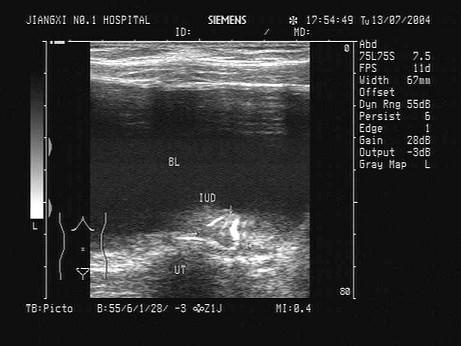

根据某患者子宫B超检查声像图,最可能的诊断为?(?)A.子宫肌瘤B.正常子宫C.节育器穿孔D.节育器下移E.子宫肌层钙化

问题 根据某患者子宫B超检查声像图,最可能的诊断为?(?)

选项 A.子宫肌瘤 B.正常子宫 C.节育器穿孔 D.节育器下移 E.子宫肌层钙化

答案 C